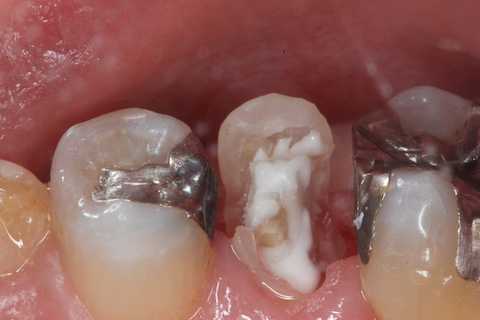

今日の充填治療55(遠心隣接面カリエス) 2023.12.21